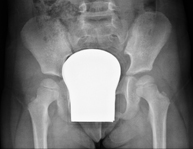

- Pelvis X-ray

This procedure uses X-ray imaging to examine the pelvis, especially the pelvic bones.

- Sacroiliac X-ray

This procedure uses X-rays to examine the sacroiliac joints and rule out inflammatory, traumatic or degenerative diseases.